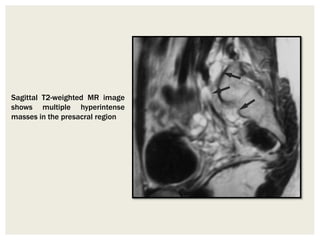

Sagittal T2-weighted MR image

shows multiple hyperintense

masses in the presacral region

Sagittal T2-weighted MRimage shows multiple hyperintense masses in the presacral region